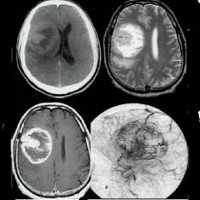

КТ: на КТ без КВ у всех 10 пациентов опухоли имели низкую плотность; при КУ в 8 случаях имело место незначительное накопление КВ; в 5 из 10 случаев были обнаружены кальцификаты на КТ. 6 из 10 опухолей располагались в височных долях (такое преимущественное расположение было отмечено во многих, но не во всех сериях наблюдений), а 4 были в лобных долях. Опухоли часто имели на КТ кистозный характер, но при этом на операции они могли быть плотными. Масс-эффект наблюдается редко (указывает на медленный рост).

МРТ: на изображениях в Т1 режиме сигнал высокий, в Т2 режиме - низкий. Кальцификаты имеют низкий сигнал в обоих режимах.

ЦАГ: демонстрирует объемное образование, лишенное сосудов, или с незначительной васкуляризацией.

Визуализационные находки отражают различные закономерности роста, которые демонстрирует данная опухоль. Частично кистозное образование с муральным узлом, усиливающемся при контрастном усилении, наблюдается в 45% случаев. Также они могут быть в виде солидного образования, распространяющееся на вышележащие извилины. Инфильтрация несвойственна, при наличии отражает высокую степень злокачественности.

Часто неспецифические признаки объемного образования. Среди общих можно выделить:

- изо- или гиподенсное;

- кальцификация в 35%;

- ремоделирование кости или ее истончение может указывать на медленный рост опухоли;

- контрастное усиление в 50% случаев (вовлекается и солидный некальцифицированный компонент).

- Т1: солидный компонент, изо- или гипоинтенсивный;

- Т1 С+: контрастное усиление солидного компонента варьирует;

- Т2:

- гиперинтенсивный солидный компонент;

- вариабельный сигнал кистозного компонента в зависимости от содержания белков и продуктов крови;

- перитуморальный отек на Т2/FLAIR не свойственен;